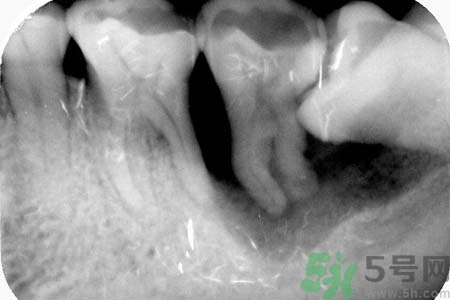

智齒的價格是根據(jù)具體的難易程度來決定的,難度越大價格也就越高,具體的收費(fèi)標(biāo)準(zhǔn)還需要根據(jù)當(dāng)?shù)氐南M(fèi)水平以及醫(yī)院的收費(fèi)標(biāo)準(zhǔn)來定的。智齒很少有能長好的,長好的是不需要拔除的,但正常要么就是長不出來,要么就是長不正就需要拔除。牙齒要盡量保留,能不拔則不拔。由于智齒位置較為隱蔽,結(jié)構(gòu)較為復(fù)雜,因此拔智齒較普通的拔牙難度大,那么拔智齒要多少錢就會相對較高,而且還根據(jù)患者的個體差異有著一定的區(qū)別。一般拔一顆智齒從幾十到幾百的都有,主要是看患者智齒長的情況。

針對長歪了的智齒,專家建議及早的拔智齒處理,至于拔智齒多少錢,一般來說拔智齒多少錢在150—300元左右,具體根據(jù)智齒的拔除難易程度而定,如果智齒阻生較為嚴(yán)重的話,在拔智齒前還需要拍x光片以了解智齒及鄰牙的具體結(jié)構(gòu),這種情況下,拔智齒多少錢相對要貴一些。